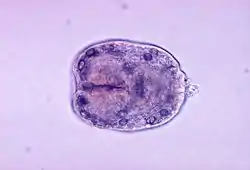

Ехінокок (Echinococcus) — рід цестод ряду циклофіллід (Cyclophyllidea). Дорослі особини паразитують у кишечнику псових (собак, вовків, шакалів, лисиць тощо), рідше зустрічаються у котів. Личинки ехінококів — небезпечні паразити людини, що спричинюють захворювання ехінококоз та альвеококоз.